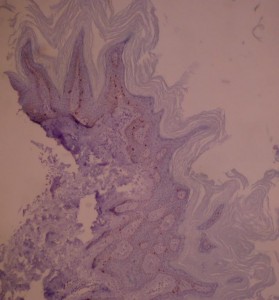

Ki-67 staining of an acantho-hyperkeratotic type of SK. On the last picture, most of the basal staining comes from the accumulation of pigment as the clinical image suggests.

Ki-67 staining of an acantho-hyperkeratotic type of SK. On the last picture, most of the basal staining comes from the accumulation of pigment as the clinical image suggests.

Ki-67 staining of an acantho-hyperkeratotic type of SK. On the last histological picture, most of the basal staining comes from the accumulation of pigment as the clinical image suggests.